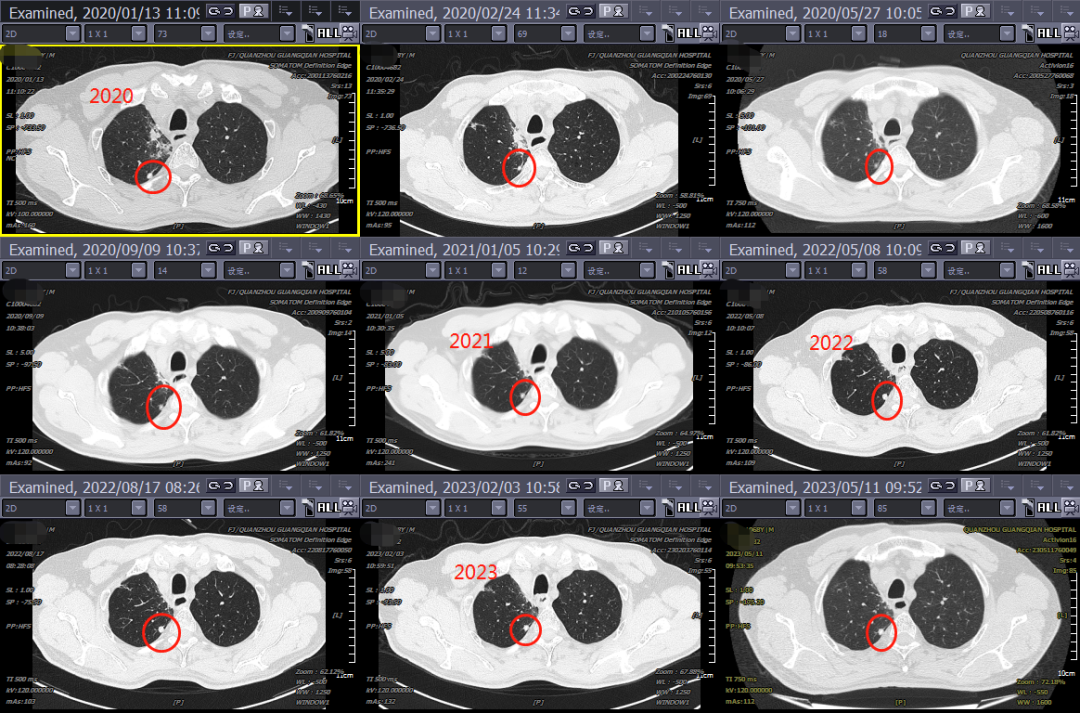

期间,接诊了一位被“肺结节”困扰多年的患者。孙晓江教授通过将2020年的影像资料与近期的胸部薄层CT进行耐心细致的对比,并在我院肿瘤放疗三区医疗团队的共同研讨下,判断为良性结节。听到这个消息后,患者如释重负,“真的非常感谢你们这么认真专业地为我诊断!悬着的心终于可以放下来了!”随即,孙教授为其科普了良性肺结节的相关知识后提出治疗建议。